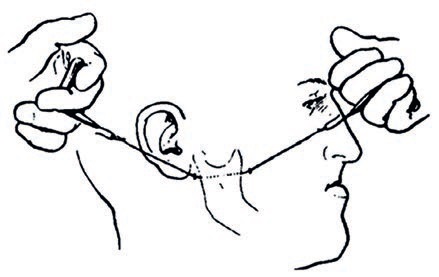

Łączne leczenie ortodontyczne i chirurgiczne ciężkiej wady zgryzu klasy III ze zgryzem krzyżowym przednim i tylnym

W niniejszej pracy kazuistycznej przedstawiono przypadek dorosłego pacjenta z ciężką szkieletową wadą zgryzu klasy III, z ewidentnym niedorozwojem szczęki i nadmiernie rozwiniętą żuchwą, co powodowało zgryz krzyżowy przedni i tylny, a także przesu...

60 lat innowacji w biomechanicznej chirurgii ortognatycznej: stan wiedzy i kierunki na przyszłość

Słowa kluczowe: chirurgia ortognatyczna, obustronna strzałkowa osteotomia żuchwy, chirurgia twarzoczaszki, staw skroniowo-żuchwowy, zaburzenia stawu skroniowo-żuchwowego Keywords: orthognathic surgery; bilateral sagittal split osteotomy; craniofac...